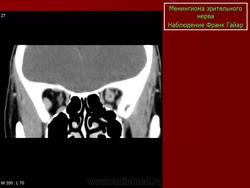

КТ-семиотика

На КТ срезах без контрастного усиления менингиома зрительного нерва выглядит изоденсной. Типично наличие линейных или точечных обызвествлений. Симптом «трамвайных рельс» отражает накопление КВ по сторонам гиподенсного зрительного нерва или наличие обызвествлений в структуре опухоли. Как правило, наиболее дистальная часть зрительного нерва, в месте его вхождения в глазное яблоко, не содержит обызвествлений.

При исследовании необходимо определить расположение бляшковидной менингиомы относительно бугорка турецкого седла и пластинки клиновидной кости, так как данный тип опухоли может распространяться интракраниально через канал зрительного нерва. КТ не позволяет адекватно визуализировать интракраниальное распространение опухоли, которое может привести к развитию двусторонней слепоты.